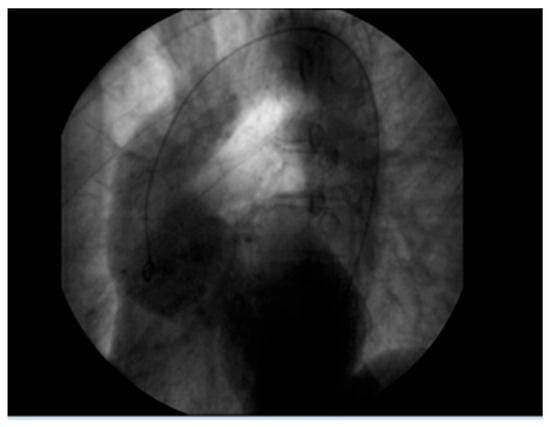

A 61-year-old patient with a history of probable Marfan syndrome was examined after referral from the treating physician because of hyperthyroidism. The tentative diagnosis of Marfan syndrome was set two decades ago based on the patient’s phenotype and a personal record of a Sinus of Valsalva aneurysm. The phenotype included a tall and lean statue, high-arched palate, crowded teeth, arachnodactyly, and divergent strabismus (Figure 1). The patient gave informed consent for the publication of his photo. The patient’s height was 188 cm, and his current weight was 88 kg. At the age of 49, a diagnosis of a 7 cm Sinus of Valsalva aneurysm was made (Figure 2), accompanied by concurrent grade 3 to 4 aortic valve insufficiency. The aortic aneurysm’s Z-score was 7.6, considering the patient’s sex, age, height, and weight. Previous surgical intervention involved an aortic valve replacement. Six years later, at the age of 55, the patient was hospitalized for an infrarenal abdominal aorta aneurysm measuring 4.9 cm, which was managed with endovascular repair and stent placement (Figure 3). Other medical history included an ischemic stroke in the right middle cerebral artery at age 56, attributed to insufficient anticoagulation in the context of a prosthetic aortic valve. The stroke did not result in any lasting neurological deficits. The patient did not present with cerebral aneurysms and had no history of arterial hypertension, hypercholesterolemia, diabetes mellitus, or active smoking.

Figure 2. Aortic root aneurysm of 7 cm visualized on coronography.